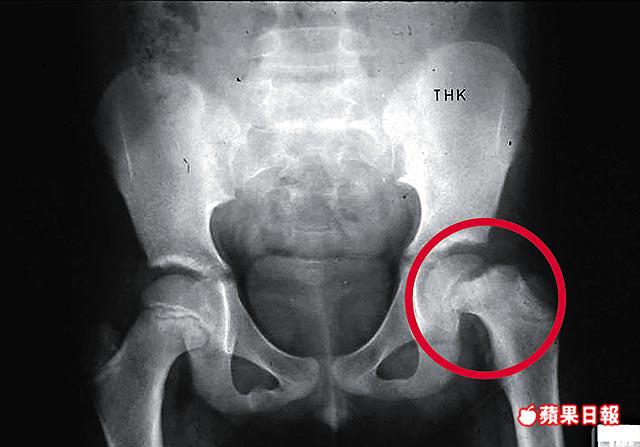

【本報訊】肥胖青少年若出現八字腳、膝蓋及髖關節痛楚,或要分開雙腳緩緩坐下才能避過疼痛,便有機會患上股骨頭生長板滑脫症候群,患者雙腳活動能力受影響,更可在數月內惡化至不能步行,要以輪椅代步,若延誤治療,甚至會永久傷殘。兒童骨科醫生指出,隨着兒童肥胖人口上升,患者也會增加,故提醒兒童及青少年要保持標準體重。 記者:梁瑞琼

股骨即大腿骨,是人體中最大的長管狀骨,上端朝向內上方,其末端膨大呈球形,叫股骨頭,與髖臼連接。

香港港安醫院兒童骨科專科醫生李閏海指出,股骨頭生長板滑脫症候群的成因不明,估計由肥胖、荷爾蒙失調及創傷引致,發病年齡為10至15歲,約25%人更會雙邊發病。患者股骨架在髖關節的生長板因發育而變得寬闊,由於該處是軟骨,可承受的力度有限,若患者過重,易令股骨移位。

李閏海指,此病的發病率約為十萬分之一,但隨着肥胖人口增加,約五分一兒童屬過重,估計患者人數將有增無減。他指,患者初時會出現膝蓋疼痛,痛楚會蔓延至腰部、腹股溝及大腿,若生長板不斷移位,雙腳會向外彎曲,導致八字腳及腿長縮短,走路時要一拐一拐,更不能像一般人「合埋腳坐」。